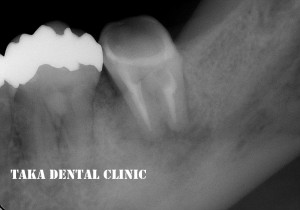

詳しい診査の後、根の治療を開始し、3回目で最終の詰め物をしました。この時には、すでに膿の袋も消失しておりました。

↑治療終了後